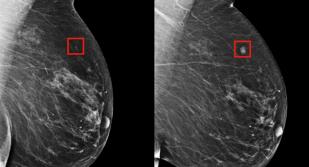

السيدة سهام بسباق مع الزمن لعلاج سرطان الثدي

السيدة سهام ارملة تعيش مع أخيها محدود الدخل وأسرته في مصر بعد أن لجئوا من سوريا تعاني من مرض الضغط ...

الأم سمية حياتها بين التوحد والورم

كغيمة سوداء يأتي مرض السيدة سمية لتطوف فوق رأسها وتثقل همومها بورم الثدي الايسر وتترجى الله عافيتها لتظل راعية لأطفالها ...